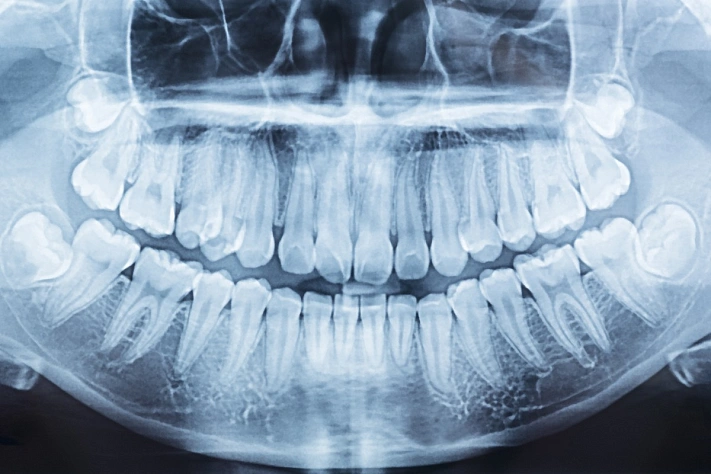

В Подмосковье врачи удалили молочные зубы 24-летней пациентке. Молодая девушка обратилась в больницу с жалобой на подвижность зубов.

При осмотре стоматологи выяснили, что зубы подвижны, поскольку являются молочными. Кроме того, они мешали вылезти постоянным коренным зубам.

Пациентка знала, что у неё не сменились твёрдые образования, но не ходила к врачам из-за отсутствия дискомфорта. Стоматологи удалили молочные зубы, поскольку на рентген-снимке были видны зачатки коренных.